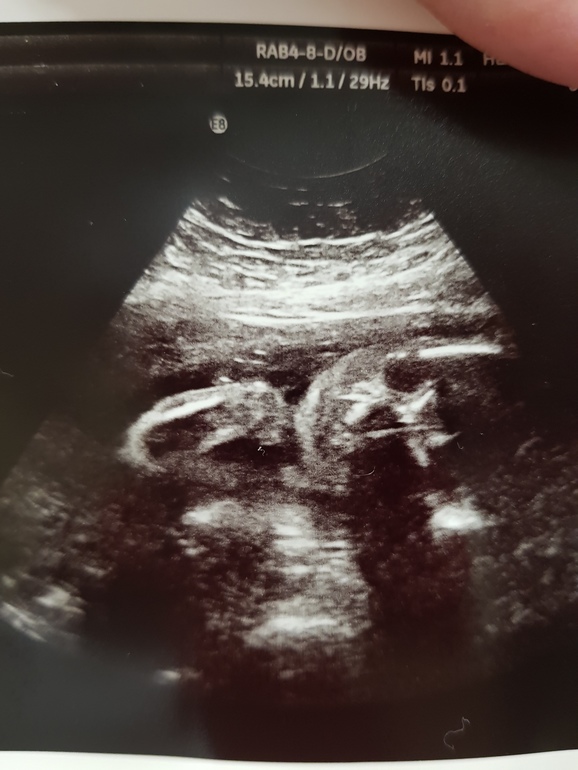

Сегодня были на узи проверить как там мои отеки и плацента, отеков слава богу не увидили (не зря мучаюсь без солененького))))) плацента низковато могла бы быть и повыше 5см при норме от 7ми.... Но сказали поднимиться еще, надеюсь))) /Маленький мой то активничает то спокойный как удав, весим уже 800гр вот такой мужечечек все узи ручки к личику жал))) ну и фоточка нашего младшенького в задумчивой позе подпер кулачком подбородок)))) на память наши 25 неделек) :